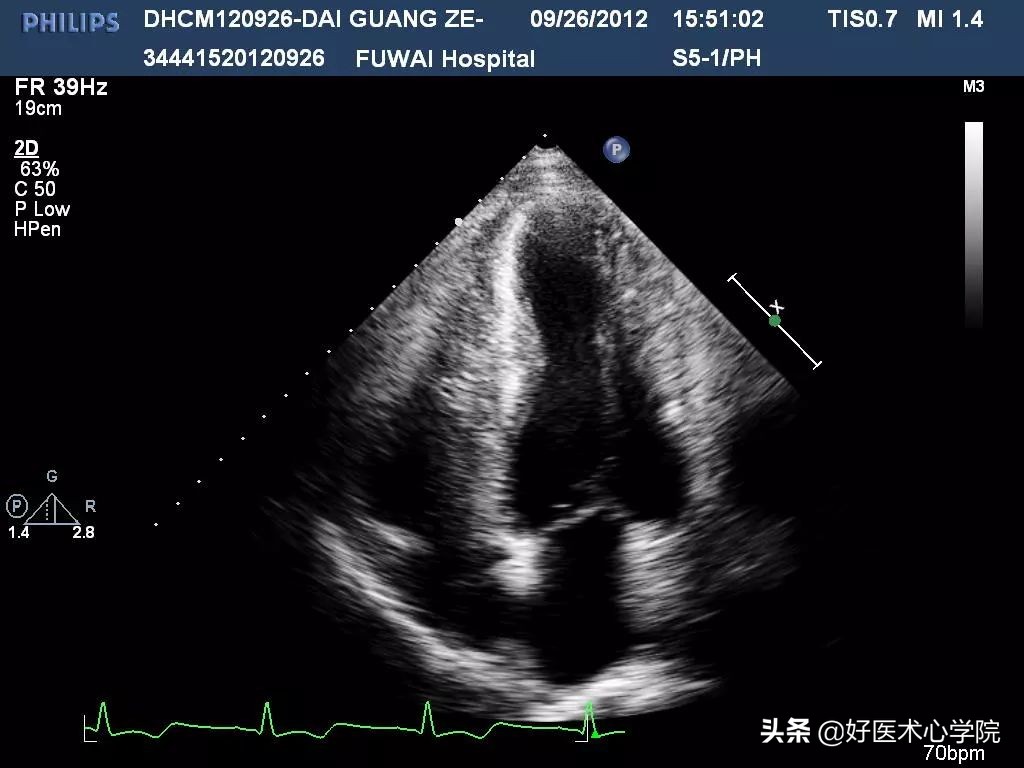

心脏彩超:LA:42mm,LV:51mmLVEF:47%,左房增大。左室壁增厚,以中部增厚为著,最厚处约31mm,室壁回声粗糙,运动减低。收缩期左室中部狭窄。心尖部室壁变薄,向外膨出,范围约41x40mm,可见反向搏动。左室腔呈“葫芦形”。

心脏超声诊断:梗阻性肥厚型心肌病(左室中部),左心功能减低,心尖部室壁瘤形成。

收缩期左室中部狭窄。心尖部室壁变薄,向外膨出,范围约41x40mm,可见反向搏动。左室腔呈“葫芦形”。